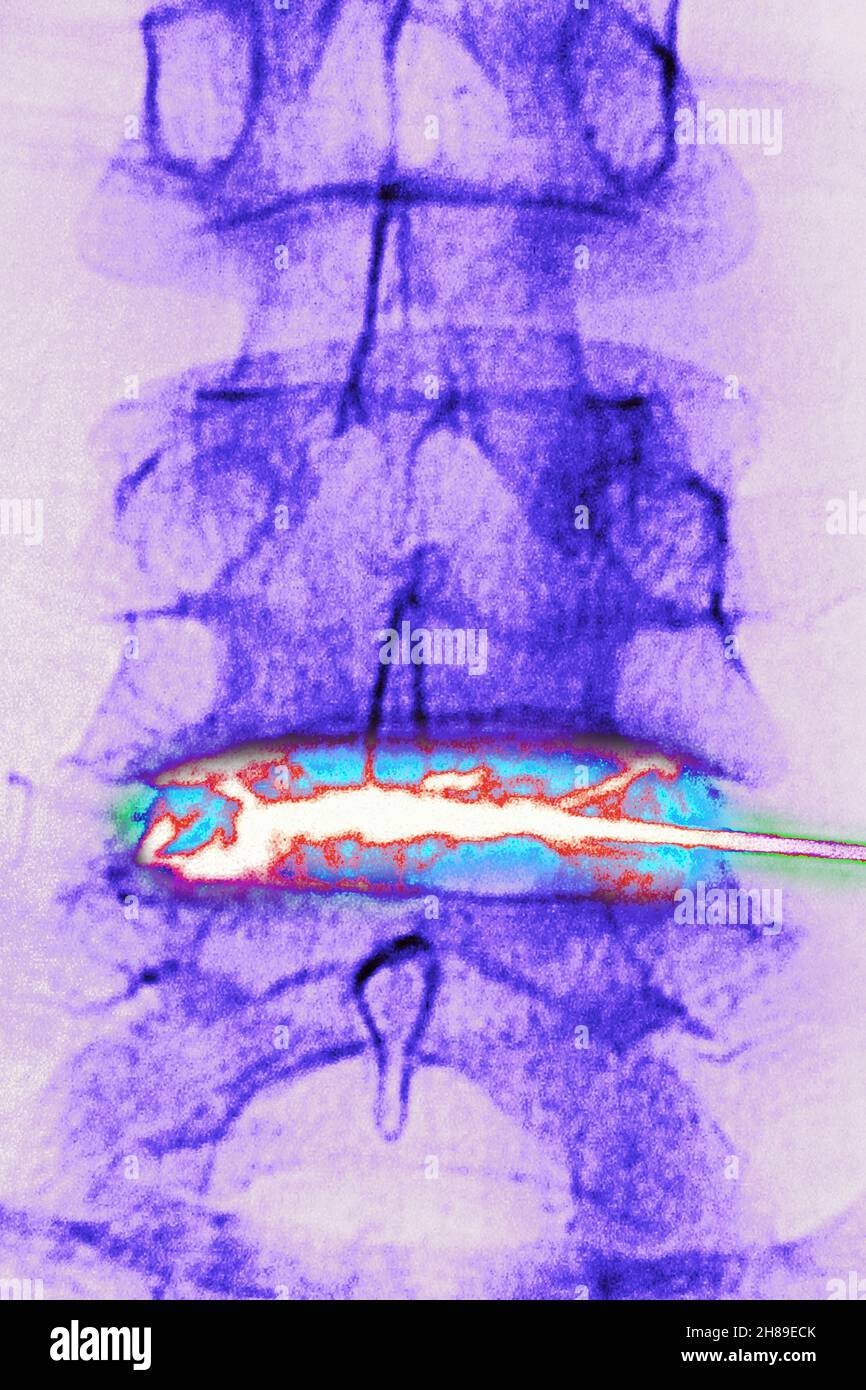

Infiltration de corticostéroïdes Banque D'Imageshttps://www.alamyimages.fr/image-license-details/?v=1https://www.alamyimages.fr/infiltration-de-corticosteroides-image452595715.html

Infiltration de corticostéroïdes Banque D'Imageshttps://www.alamyimages.fr/image-license-details/?v=1https://www.alamyimages.fr/infiltration-de-corticosteroides-image452595715.htmlRM2H89ECK–Infiltration de corticostéroïdes